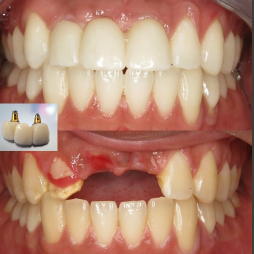

Transformations

Dental Implants closely mimic natural teeth in both appearance and function. They are exceptionally durable and can last a lifetime with proper care.